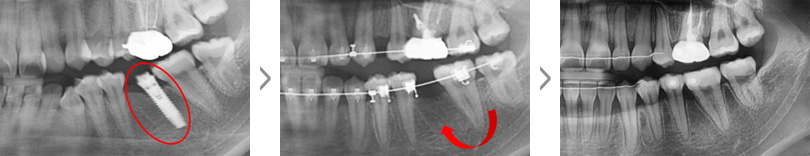

아랫니가 앞니보다 바깥쪽으로 위치한 증상을 바로잡고 빠진 윗니를 수복하기 위해 내원한 37세 남성입니다.

검사 결과 위쪽 영구치 3개 결손 된 상태였으며, 아래턱이 전방 위치된 주걱턱(골격성 3급 부정교합)으로 진단

하였으나 양악수술 없이 치료를 원하셔서 치아교정과 임플란트 치료를 병행하였습니다.

약 2년 간의 교정 치료 후 정상적인 앞니 배열과 임플란트 식립에 필요한 공간이 확보되어 보철 치료를 한 후

교정 장치를 제거하였습니다. 거꾸로 물려 정상적인 기능이 어려웠던 앞니의 심미적, 기능적 회복이 동시에

이루어졌습니다.